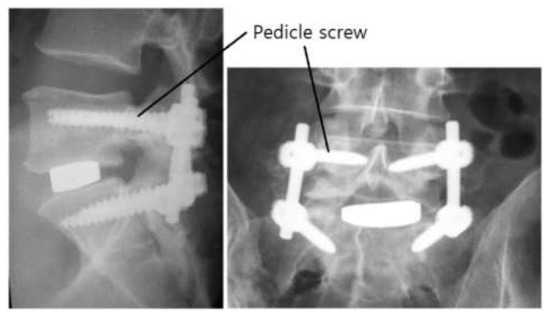

Patients suffering from the above-mentioned disease is usually treated via surgical methods using spinal decompression or spinal fusion. Pedicle screws are usually applied in spinal fusion surgery [4,5,6]. The spine has many vertebrae, and two or more can be fused or supported by using pedicle screws and a linking mechanism. Figure 1 shows post-operative radiographs after a lumbar interbody fusion for degenerative disc disease [1].

Figure 1. Radiographs after a lumbar interbody fusion surgery for degenerative disc disease.